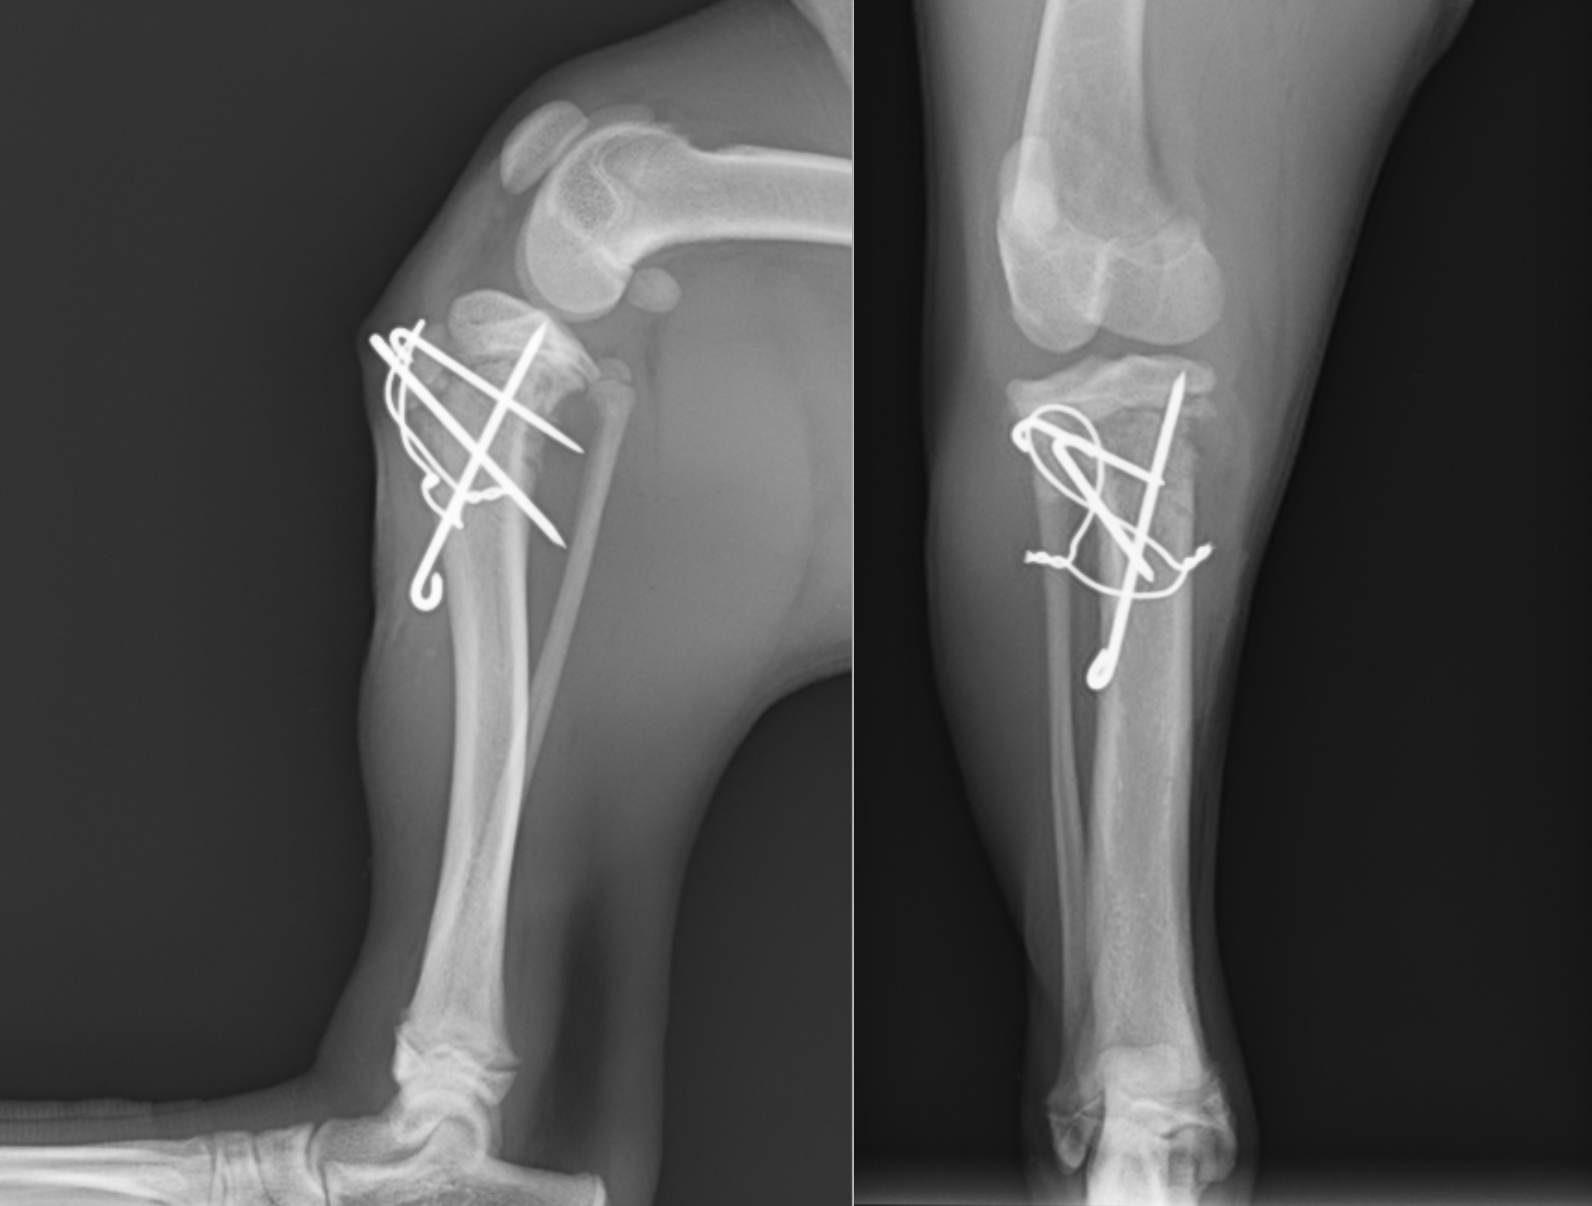

術後のレントゲン画像です。ずれていた骨片は正しい位置に戻っているのがわかると思います。左下から右上に打っているピンは、骨片が右にずれないようにするストッパーのような役割をしています。

手術ではまず、ずれてくっついてしまった骨を剥がすところから始まります。1週間でもかなり癒着が進んでいたため、それを一度剥がし、正しい位置に戻しました。骨折の固定には一般的にプレートスクリューを用いることが多いですが、成長板骨折の時は別で、成長板をまたいだ固定は禁忌とされているため(成長が阻害され骨が伸びなくなってしまう)、キルシュナーワイヤーとテンションバンドワイヤーという方法により固定を行いました。術中はCアームと呼ばれるレントゲン透視装置を用いて、正しい位置にピンが刺入されているかを確認しながら手術を行いました。